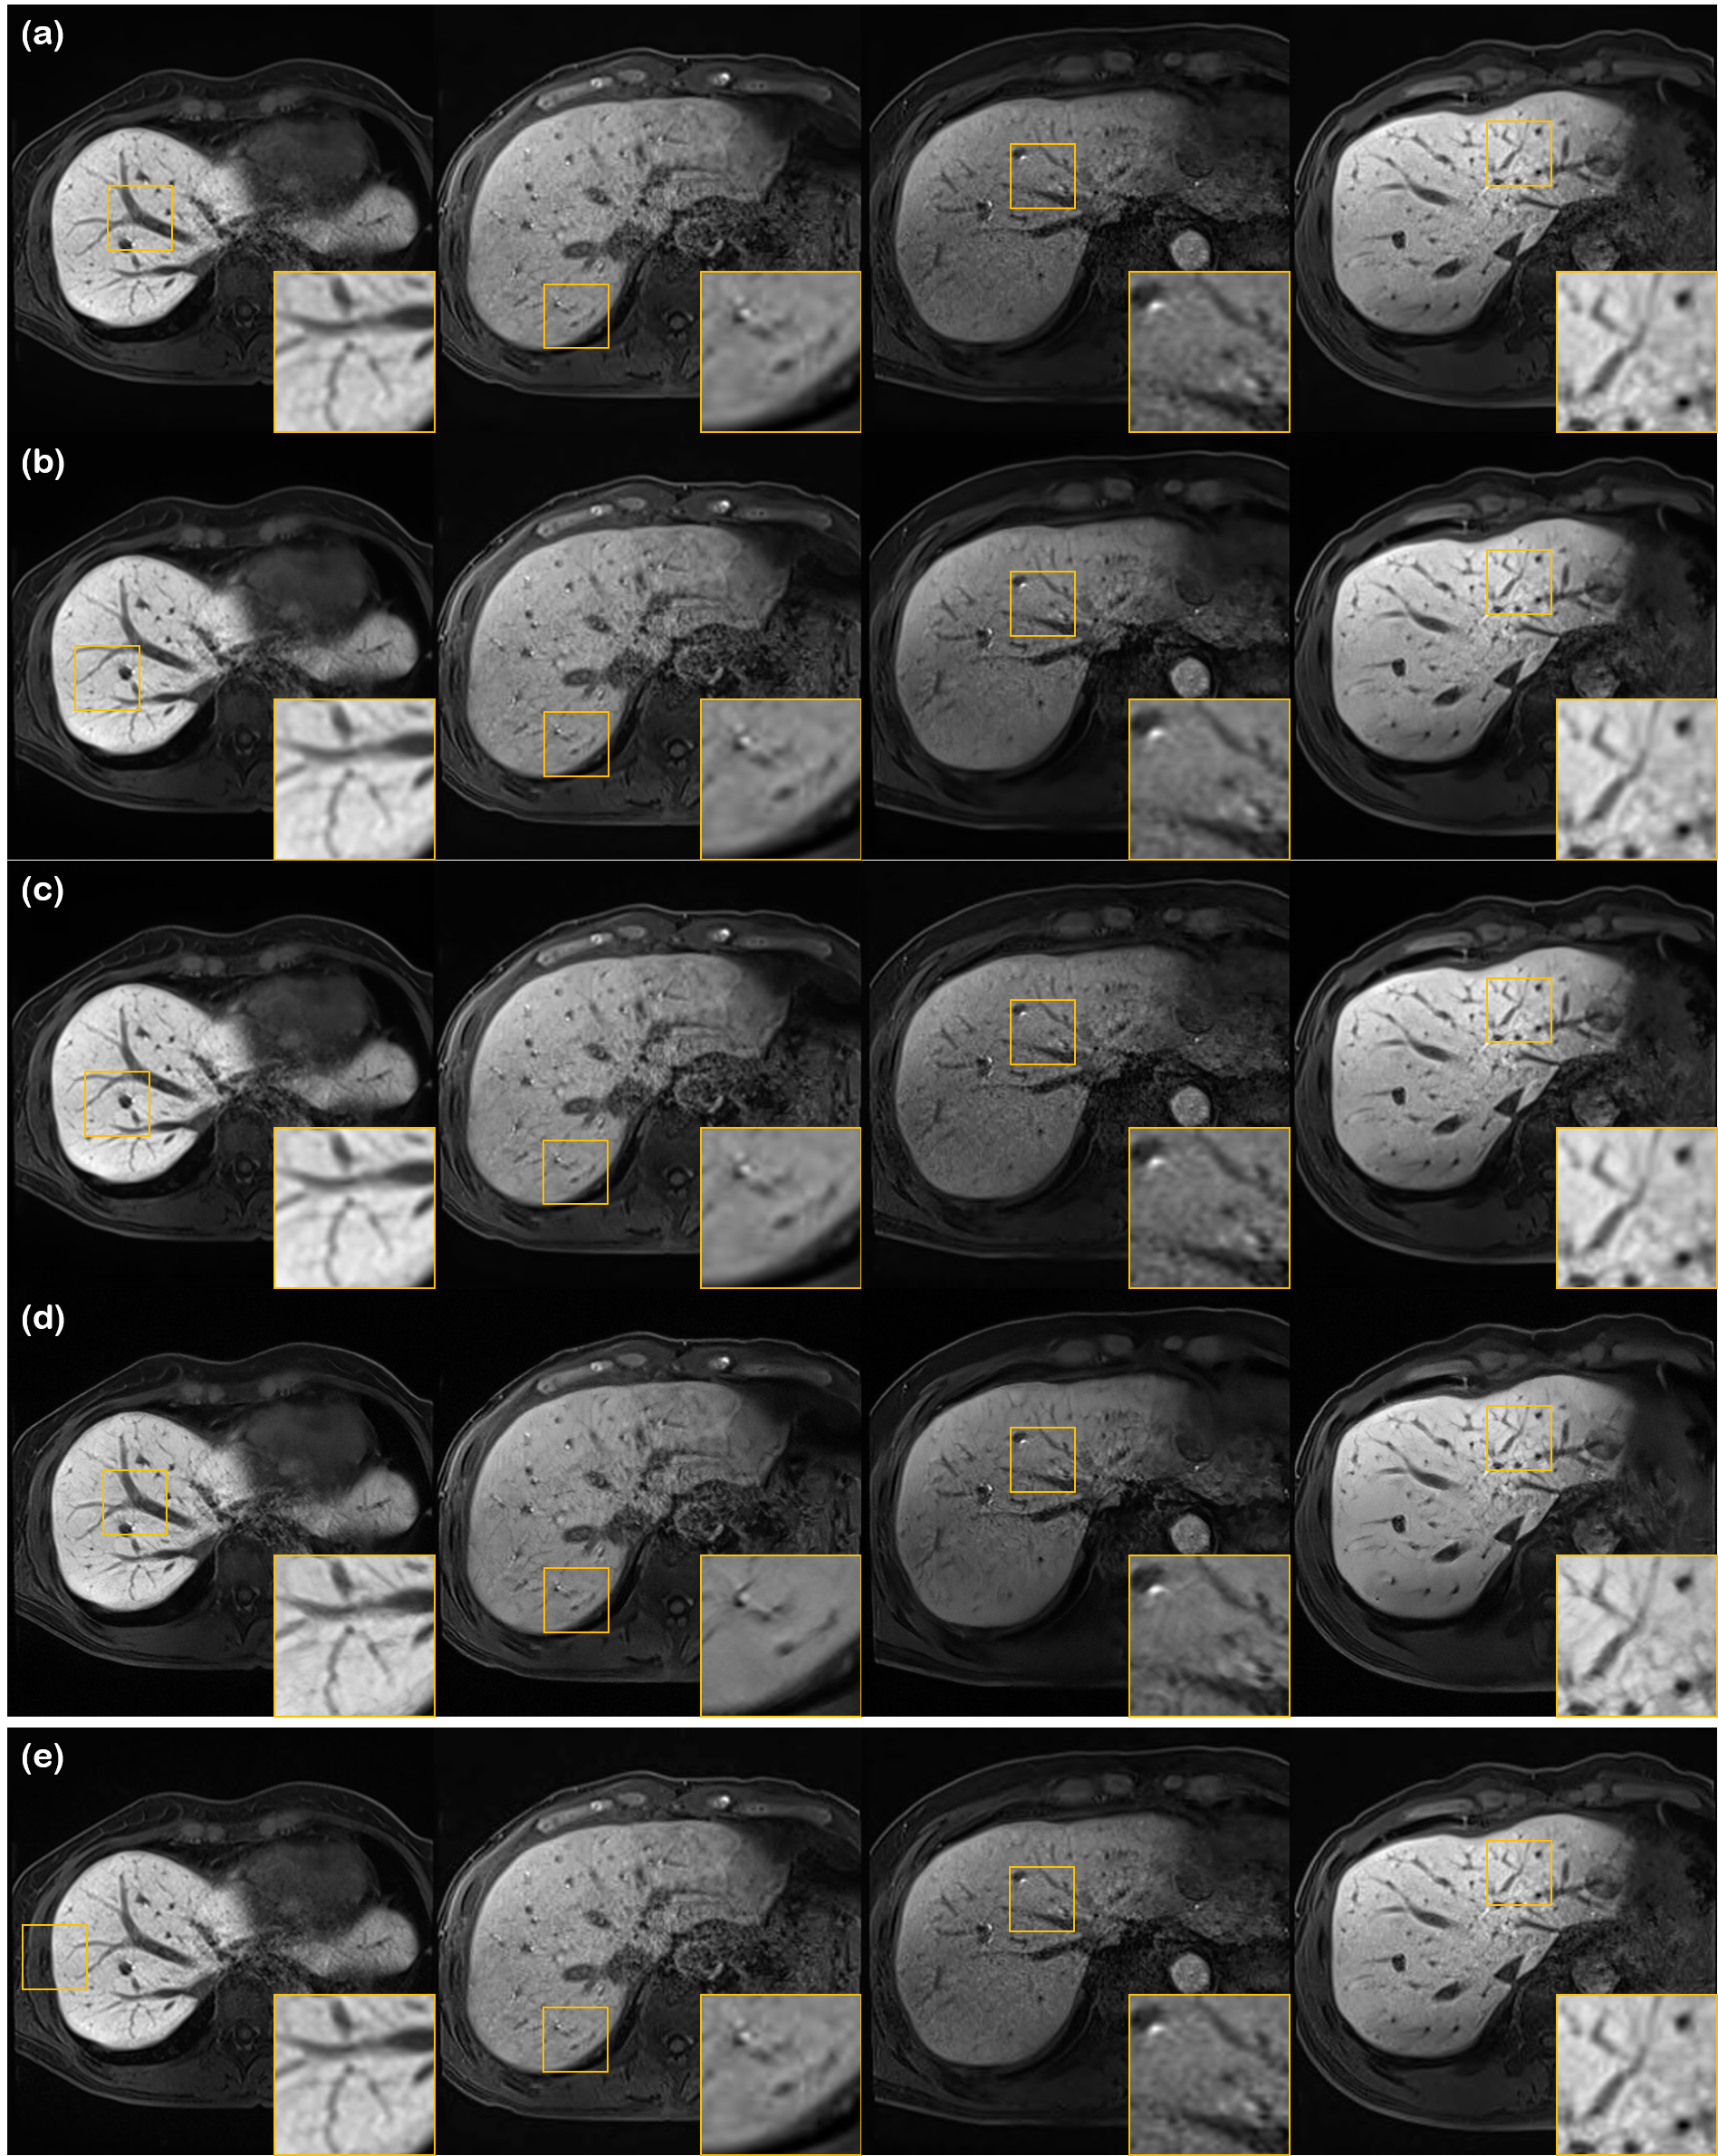

Refer to caption

Figure 3: Denoising results using various methods on different liver conditions. (a) N2N [13], (b) N2Score [15], (c) proposed method, and (d) input noisy image. Yellow boxes show results that are magnified. First row: early liver cirrhosis with hepatocellular carcinoma (HCC), second row: normal liver, third row: advanced liver cirrhosis.

Denoising results are summarized in Fig. 3, with the quantitative metrics in TABLE II. In Fig. 3, we see that our method is the only method to effectively remove the noise while sharpening the image, regardless of the given condition of the liver. This is also consistent with the metrics given in TABLE II, where our method is the highest scoring method both in terms of SNR and CNR. Notably, it can be seen from TABLE II that while all methods have higher SNR than the input such that it is statistically relevant, R2D2+ is the only method which does not compromise CNR. This can be deciphered in two aspects - 1) R2D2+ is the only method that explicitly enhances the resolution with the same network that was used to denoise the image. 2) Posterior sampling does not produce blurry output, as opposed to MMSE estimates.

From TABLE II, we do observe that self-supervised learning based methods (i.e., N2N, N2Score) have much better performance than BM3D. Nevertheless, the metrics lack far behind R2D2+, especially in terms of CNR. This can also be visually inspected in Fig. 3 (b-d). While we can see relatively clearly that denoising has taken place as opposed to the noisy input, the denoised output tend to be washed out, with unclear boundaries and vessel structures. We note that Nei2Nei performs even worse than BM3D, which we conjecture to be stemming from its poor generalization capability. For further experimental results with detailed information about the statistical analysis, together with more figures including comparisons with BM3D, see Fig. 7.

In Fig. 7, we show additional experimental results, comparing extensively with block-matching 3D filtering (BM3D) [47], Noise2Noise (N2N) [13], and Noise2Score (N2Score) [15]. It is clear from Fig. 7 (d) that the proposed method clearly outperforms all methods, by reconstructing sharp vessel structures, while removing excessive noise around such structure. All other comparison methods fall heavily behind the proposed method, especially in terms of preserving high-frequency detail.